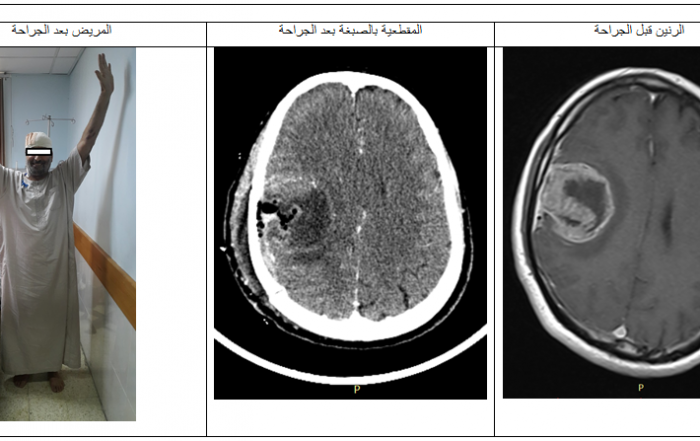

مستشفى الأوروبي يجري ثلاثة جراحات لاستئصال أورام دماغية بنجاح خلال أسبوعين